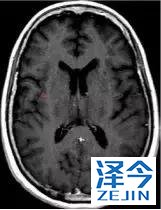

肺靶病变达到缓解,我们可以明显的看到前后的图像,病灶明显缩小了,

脑转移病变显示缩小了95%!

初始, 2018年6月 3周期 2018年8月